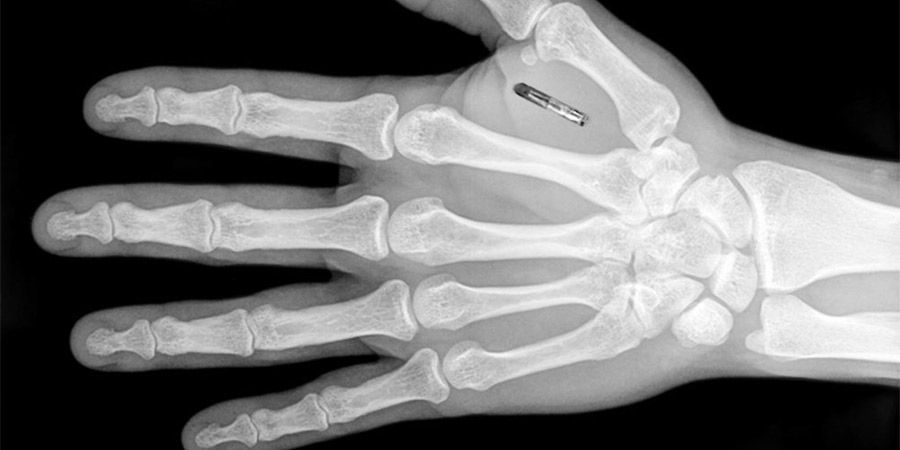

Los pequeños implantes usan una tecnología llamada Near Field Communication (NFC, comunicación de campo cercano), similar a los pagos sin contacto con tarjetas de crédito y celulares. Cuando son activados por un lector a unos pocos centímetros, una pequeña cantidad de datos fluye entre los dos dispositivos. Los implantes son “pasivos”, lo que significa que contienen información que puede ser leída por otros aparatos, pero no pueden leer información.}